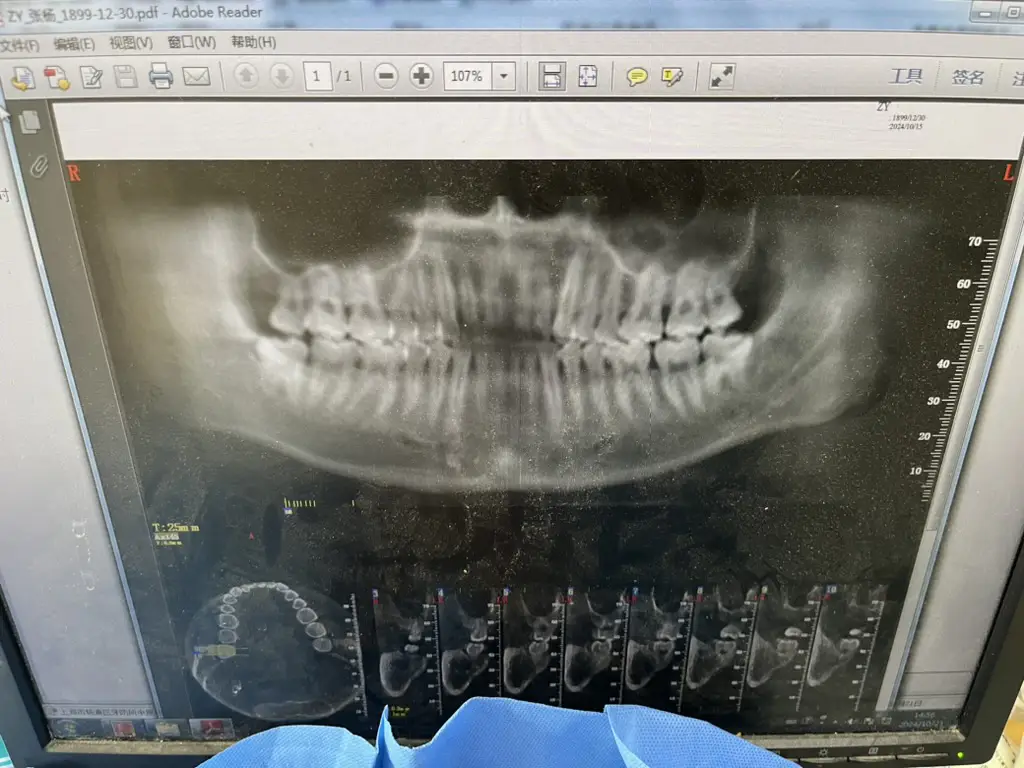

牙疼,具体来说是牙龈疼。疼得我吃嘛嘛不香、非常心烦,于是在一个平平无奇的周三,我去了一趟牙诊所。买了一个99¥的洗牙套餐,拍了一张牙片:

牙医说,我的(右下侧,牙片里是左下侧)智齿没有完全长出来,所以覆盖的牙龈和牙齿之间的缝隙很容易藏污纳垢。再加上我清洁不到位,所以就反复发炎。

开了一些治疗牙龈发炎的替硝唑片,拍了一个更昂贵的牙CT: